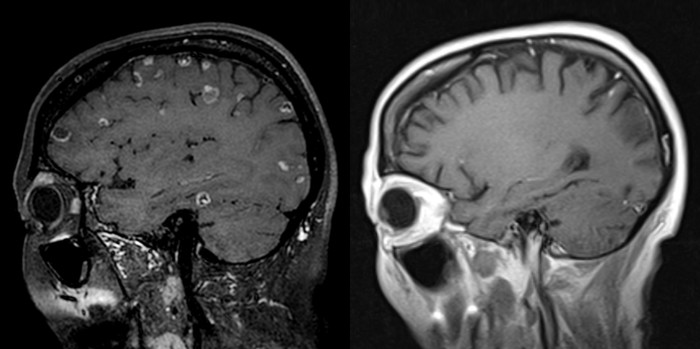

| ▲ 명역항암치료 및 표적치료 후 뇌로 전이된 암세포들이 모두 소멸됐다. |

결과는 놀라웠다. 암세포가 치료에 반응을 보이기 시작하더니 뇌와 폐에 있던 종양들이 약 10개월에 걸쳐 모두 사라졌다.

1개월 시한부 선고를 받은 말기 암환자가 거의 완치수준의 기적이 일어난 것이다.